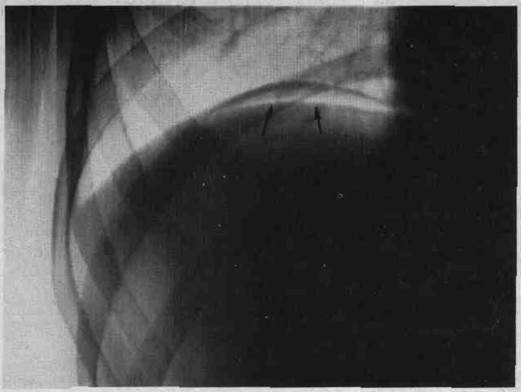

1) Назовите признак перфорации полого органа при повреждениях живота и укажите его на рентгенограмме.

1) Пневмоперитонеум. Признак пневмоперитонеума на рентгенограмме – наличие воздушной прослойки между куполом диафрагмы и тенью печени справа (признак перфорации полого органа).